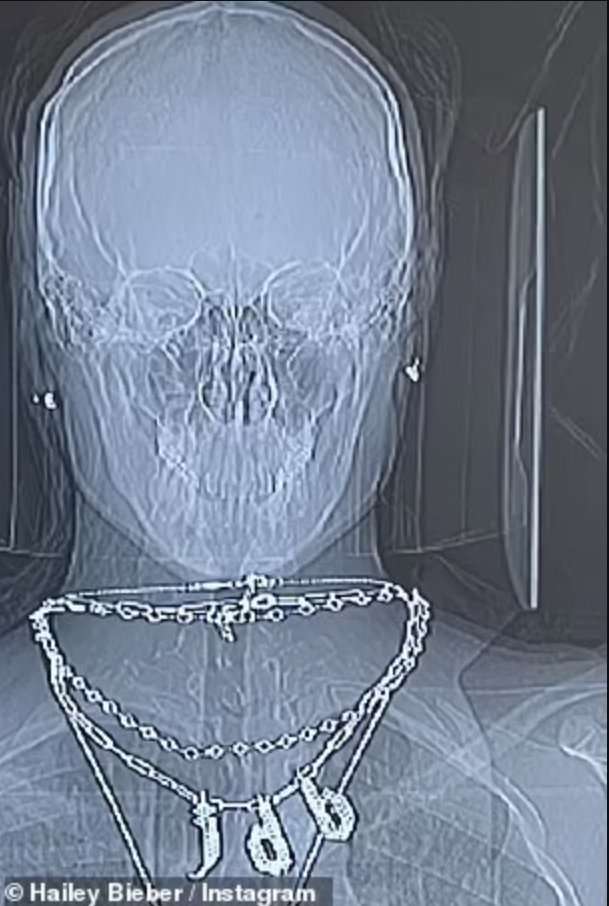

>>1

このターミネーターレントゲン撮った時の話?![ジャスティン・ビーバーの妻、“心臓手術”成功に感謝]()

「ちょうど昨年のこの時期、私は心臓にできた穴を塞ぐための治療を受けた。PFOと呼ばれるもので、一過性脳虚血発作の後にできたもの」

「これが見つかり塞がったことに本当に感謝している。素晴らしい医師たちに本当に感謝。1年が経った今、強くて健康だと感じている」

男とか言われているけど私は好きな顔だしスタイルも好き。

ファッションもスポーティ似合ってて良いと思う+7

ジャスティン・ビーバーの妻ヘイリー・ビーバー(26歳)が、心臓手術の成功に感謝の意を述べている。昨年、脳卒中のような症状を引き起こし入院し、一過性脳虚血発作により脳に小さな血栓があることが判明したヘイリー。その血栓が心臓に移動していたことから、卵円孔開存(PFO)の閉鎖治療を受けていた。